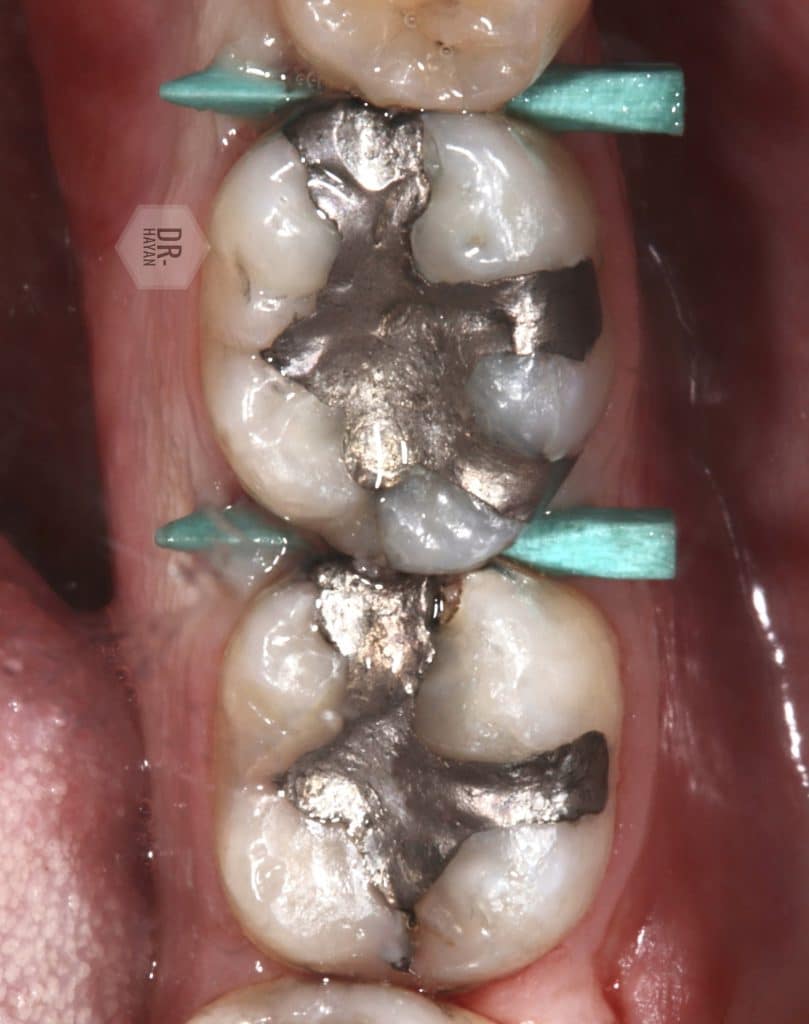

Initial view :

-Old amalgam filling

- Open margin

- recurrent caries

-pain with chewing